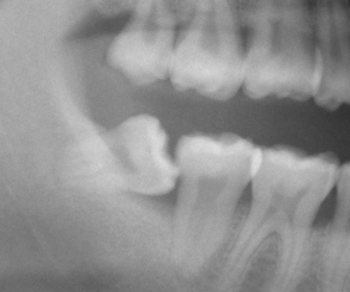

上のレントゲン写真の左下の歯が「親知らず」ですが、イメージとして、、、 |

|